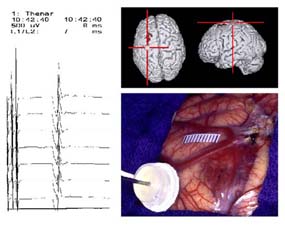

Das freigelegte Hirn wird dazu mit sterilen Plättchen markiert. Jeder Punkt wird anschließend elektrisch stimuliert.

Im Bereich des motorischen Systems erhält man aus der Muskulatur der Extremitäten ein Signal. Mit dessen Hilfe kann während der gesamten Operation am offenen Hirn die Funktion der für die Körperbewegung wichtigen Zentren überwacht werden.

Diese Untersuchungen sind nicht schmerzhaft und mit keinen weiteren Risiken verbunden. Die gewonnene Information kann für den Ausgang einer Operation jedoch von entscheidender Bedeutung sein. Denn die Gefahr einer Verschlechterung von Sprache oder Bewegung kann mit Hilfe dieser modernsten Technik auf ein Minimum reduziert werden.